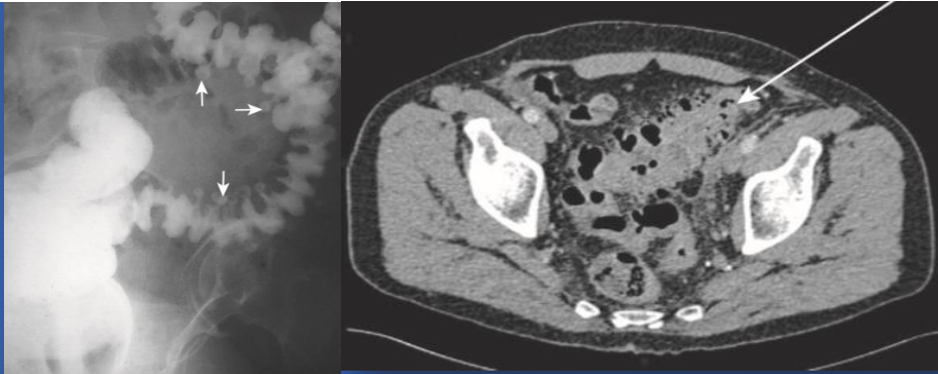

Radiology images:

Plain abdominal radiograph series

Contrast enema, * Water-soluble medium, * Mild-to-moderate uncomplicated cases

CT abdomen with contrast * Best imaging method to confirm the diagnosis. * Sensitivity and specificity 97% * Bowel wall thickening * Soft-tissue inflammatory masses * Complications, exclude other pathology